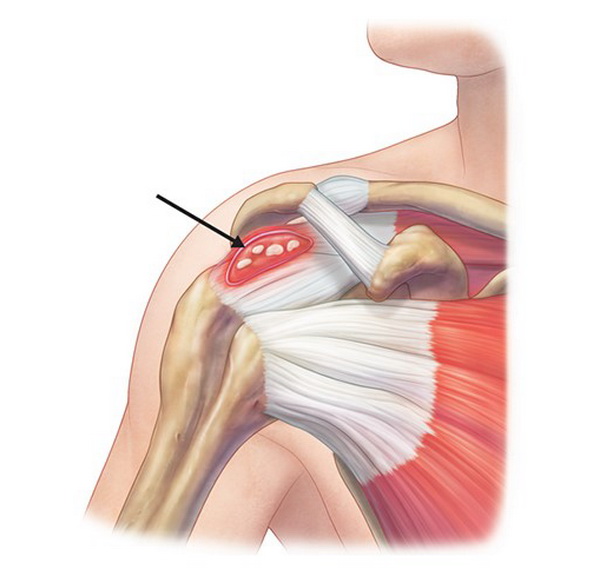

Фотографии мышц ротаторной манжеты плеча